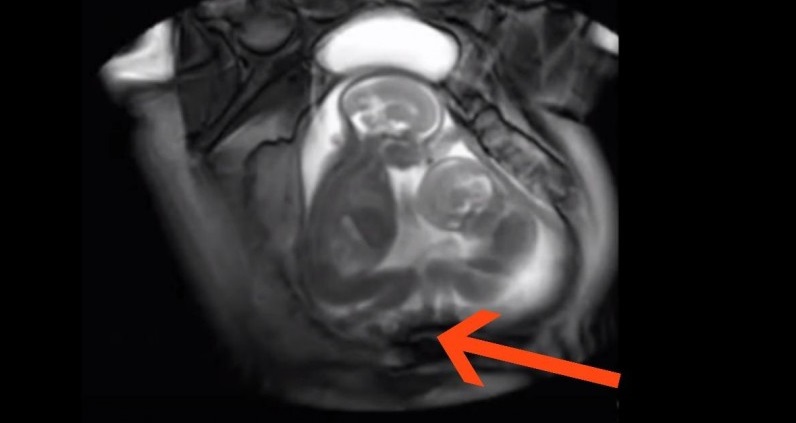

Αλλά το παρακάτω βίντεο δείχνει τι συμβαίνει ανάμεσα σε δύο δίδυμα που βρίσκονται στην κοιλιά της μαμάς τους και οι γονείς και οι γιατροί παθαίνουν πλάκα: Αυτό το βίντεο προέρχεται από ένα ερευνητικό πρόγραμμα όπου οι γιατροί προσπαθούν να μάθουν περισσότερα για την συμπεριφορά των διδύμων στην μήτρα. Είναι ξεκάθαρο ότι τα δίδυμα παλεύουν για τον χώρο μέσα στην μήτρα.

Κλωτσάνε και στριφογυρίζουν για να βρουν ελεύθερο χώρο, σχεδόν σαν δύο άτομα σε ένα στενό κρεβάτι! Τα ευρήματα αυτής της έρευνας θα μπορούσαν να βοηθήσουν τους γιατρούς να μειώσουν το κίνδυνο επιπλοκών σε εγκυμοσύνες διδύμων στο μέλλον.